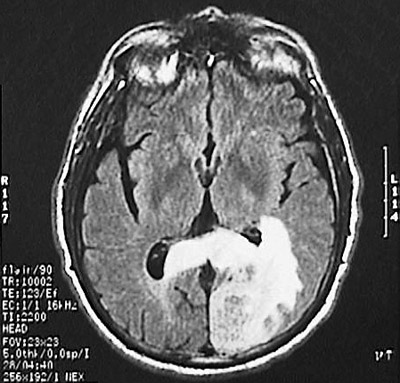

| This MRI scan of the head in axial view demonstrates a large glioblastoma multiforme involving the left occipital lobe. This is a T1 weighted scan, and the tumor is seen crossing the midline toward the right and is bright after gadolinium enhancement. |